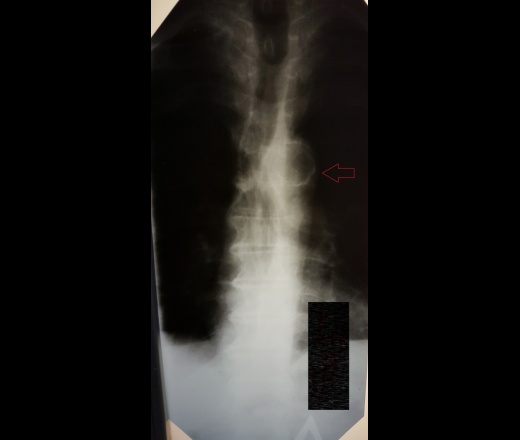

Пол пациента: Мужской пол Тип патологии: Другое Область исследования: Грудная клетка и верхние дыхательные пути Методы исследования: Rg Мужчина 78 лет. Округлая тень на уровне th5-6 позвонков в прямой проекции? ID:73016 Цель публикации: Консультация Втр, 05/09/2017 - 18:59 #1 И.Бондаренко Не на сайте Был на сайте: 1 день 11 часов назад Зарегистрирован: 13.09.2011 - 22:55 Публикации: 9206 Обызвествление аорты. Втр, 05/09/2017 - 19:02 #2 Евгений Алексеевич Не на сайте Был на сайте: 5 лет 3 дня назад Зарегистрирован: 28.06.2013 - 16:23 Публикации: 4122 Кальцинаты в стенке, в ортопроекции просвета дуги аорты. Втр, 05/09/2017 - 19:34 #3 NIL Не на сайте Был на сайте: 1 день 15 часов назад Зарегистрирован: 25.11.2013 - 20:50 Публикации: 18207 И.Бондаренко wrote: Обызвествление аорты. +1 "Слушай всех, прислушивайся к немногим, решай сам".© Втр, 05/09/2017 - 20:13 #4 Катенёв Валенти... Не на сайте Был на сайте: 7 лет 3 недели назад Зарегистрирован: 22.03.2008 - 22:15 Публикации: 54876 Интересно..., а что рентгенографировали? Ср, 06/09/2017 - 06:48 #5 В.И. Не на сайте Был на сайте: 2 месяцев 4 дня назад Зарегистрирован: 22.09.2015 - 17:55 Публикации: 2321 Всем спасибо.

Обызвествление аорты.

Кальцинаты в стенке, в ортопроекции просвета дуги аорты.